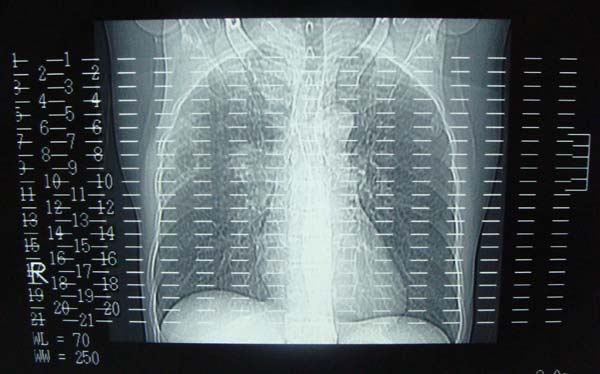

以下是引用pujunzhi在2009-6-21 21:48:00的发言:[br]右肺上叶后段见一空洞性病灶,灶周有渗出即晕征,右肺门肿大---可考虑感染性空洞和癌性空洞,先抗炎抗痨后复查并完善相关检查。有癌性空洞伴肺门淋巴结转移的可能。